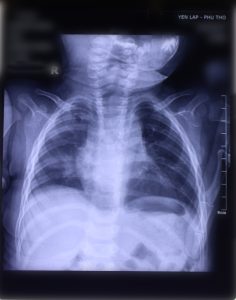

Bệnh nhi P.N.A.H (6 tháng tuổi, ở xã Mỹ Lương, huyện Yên Lập) vào viện trong tình trạng sốt cao, tím môi, gốc mũi, khò khè đờm, chảy mũi, thể trạng yếu, có nhiều cơn ngừng thở kéo dài. Theo mẹ của trẻ kể bệnh nhi đã mấy ngày nay ho từng cơn về đêm và sáng, ho nhiều đờm ,khò khè nhiều có lúc sốt cao, quấy khóc, gia đình cho uống thuốc hạ sốt và kháng sinh không đỡ. Sau khi thực hiện xử trí hồi sức tích cực, chỉ định thực hiện các cận lâm sàng Bác sĩ chẩn đoán bệnh nhi bị viêm phổi nặng/suy hô hấp.

Tuy chỉ mới 1 tháng tuổi, nhưng bé N.G.H (ở xã Đồng Thịnh, huyện Yên Lập) cũng gặp tình trạng ho khò khè, có đờm, sốt, bú kém, đến ngày thứ 3 được gia đình đưa đến Trung tâm Y tế để thăm khám. Qua thăm khám, bệnh nhi tỉnh, bú kém, sốt nóng 38 độ C, không nôn, ho từng tiếng, khò khè đờm, da xanh , niêm mạc hồng nhạt, tím nhẹ quanh môi, gốc mũi, SPO2 91%. Các bác sỹ chẩn đoán trẻ viêm phổi nặng và được xử trí, điều trị theo phác đồ, thở Oxy gọng mũi 1,5 l/p, ăn sữa mẹ bón thìa. Sau 10 ngày điều trị bệnh nhi ổn định và được xuất viện.